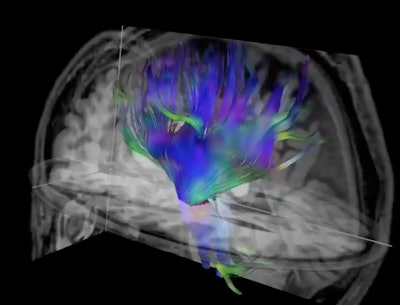

Researchers used diffusion tensor imaging, an MRI technique, to study the impact of football heading on the brain. This method tracks the microscopic movement of water molecules through brain tissue to characterize the brain's microstructure. Image and caption courtesy of the RSNA.

The researchers wanted to study the association of football heading over two years with change in brain microstructure and cognitive performance in adult amateur players. They used DTI, an MRI technique that characterizes the microstructure of the brain by tracking the microscopic movement of water molecules through brain tissue.

The team found that compared with baseline test results, the high-heading group showed increased mean, radial, and axial diffusivity in frontal white-matter regions. This group also demonstrated decreased orientation dispersion index in the right superior frontal white-matter and superior corona radiata.

Additionally, Charney's group reported that the gray matter-white matter interface on DTI-MRI appeared more blunted and had a fuzzier transition in the high-header group. They added that this may play a role in the adverse association between repetitive head impacts and cognitive performance.